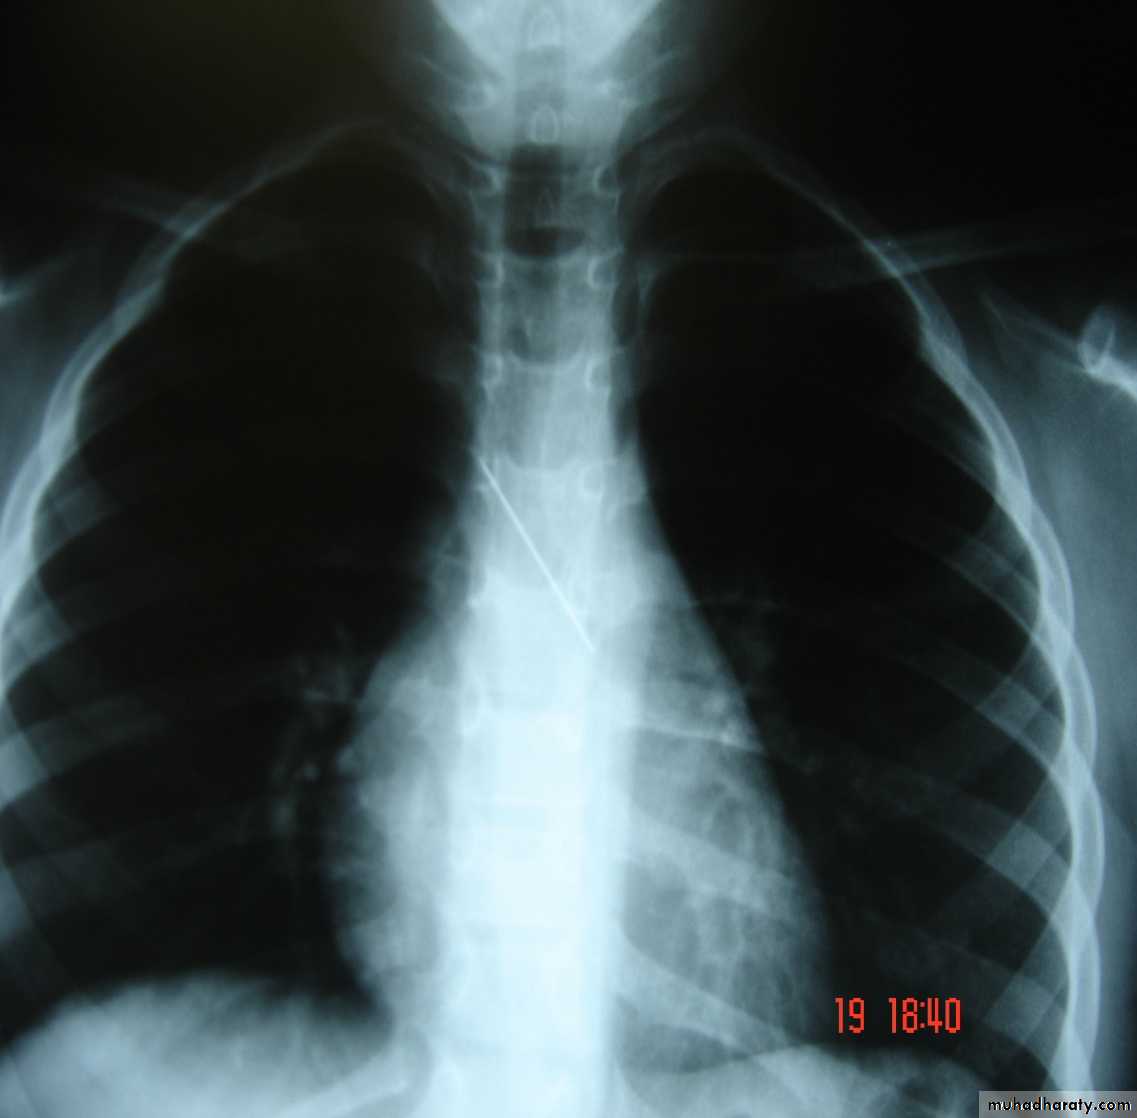

Foreign Body (RMB)